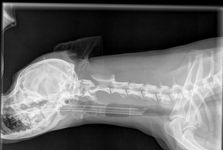

צילום רנטגן

צורת הדמיה זו הינה השכיחה ביותר. צילום רנטגן נעשה באמצעות מעבר קרני רנטגן מצד אחד של הגוף אל צידו השני, שם נמצאת הקסטה אשר קולטת את הקרניים ומתרגמת אותם לתמונה, אשר ניתן להעביר למחשב.

בזמן הצילום, חלק מרקמות הגוף לא מאפשרות לקרני הרנטגן לעבור (כגון עצמות), לעומת אויר אשר מאפשר מעבר מלא, בעוד רקמות אחרות סופגות באופן שונה את קרני הרנטגן, וכך בסופו של דבר נוצרת תמונה.

לאחר מיקום בעל החיים בתנוחה הרצויה, הצילום עצמו יתבצע תוך שניות ספורות. צילום רנטגן בבעלי חיים זהה כמעט לחלוטין לבדיקה הנעשית בבני אדם - הציוד והמכשיר הם אותו דבר , אך ההבדל הוא שלעיתים בעל החיים יהיה צריך להיות מטושטש על מנת למנוע תזוזה במהלך הצילום (מאוד דומה להדמייה של תינוקות וילודים).